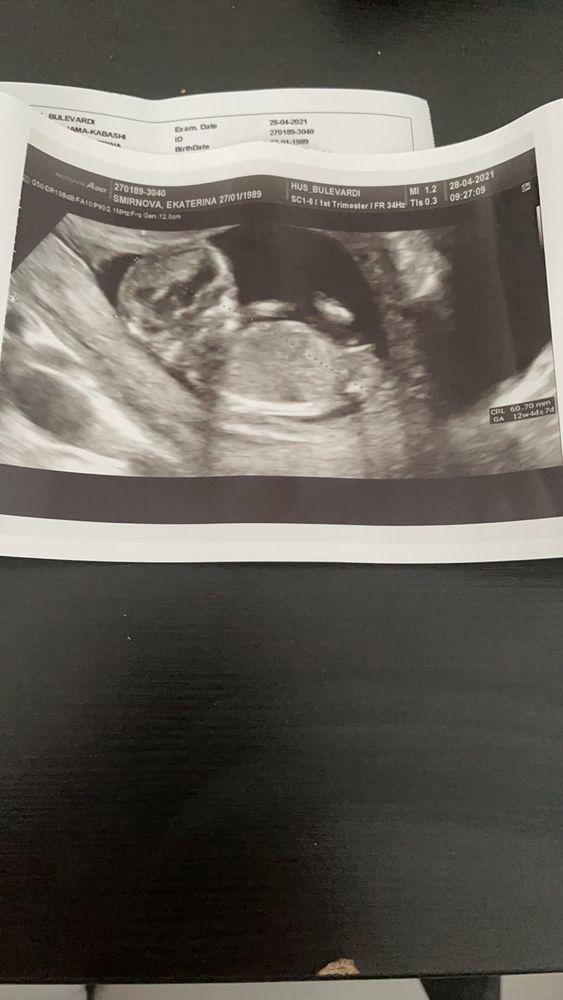

Первое узи в 12+4

УЗИ, КТГ, доплерСегодня было первое узи, врач ничего не сказала про пол. Но мне очень интересно. Кто по фотографии хорошо может определить? Посмотрим?))

Тут немного неудачный ракурс,непонятно куда бугорок смотрит...Как по мне,он смотрит вверх.У моей в 12 недель прям параллельно был,без намеков...

Мне кажется если бы был мальчик, бугорок был бы уже выше приподнят. У меня на УЗИ в 11 недель бугорок был низко, в 13,1 неделю уже стоял высоко, у Вас срок хороший, поэтому согласна с большинством, похоже на девочку 😊